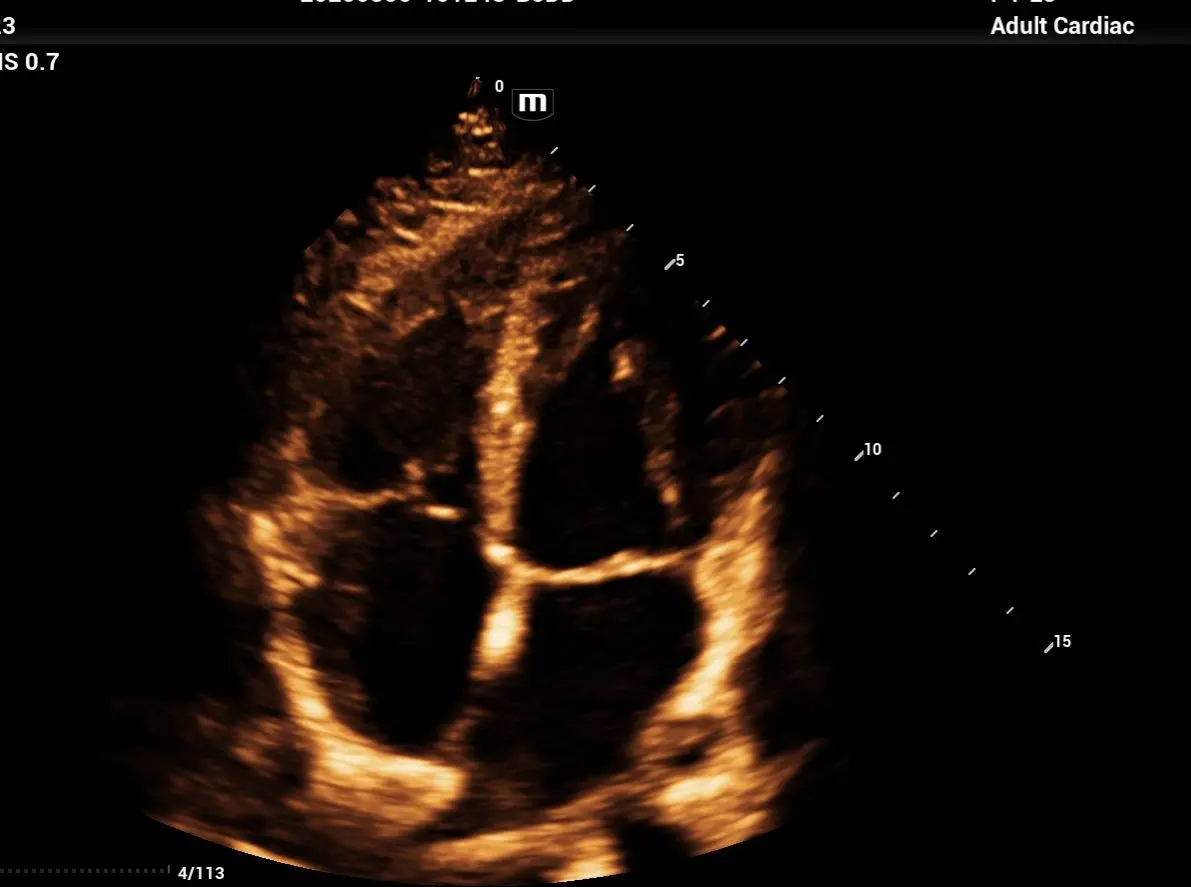

Ecocardiograma Doppler Color Transtorácico y Strain Longitudinal

Incluye perfil de lípidos 11 elementos.

Evalúa cavidades, válvulas, flujo y fuerza de contracción. Dirigido a pacientes con presión alta, dolor torácico, arritmias o revisión preventiva.

¿Qué es el Ecocardiograma ?

El ecocardiograma es un estudio de imagen cardíaca que utiliza ultrasonido para obtener imágenes en tiempo real del corazón. Es una de las principales herramientas diagnósticas en cardiología porque no es invasivo, determina cardiopatías, insuficiencia cardiaca , el flujo sanguíneo , enmerdades valvulares.

¿Qué es el Ecocardiograma Doppler con Strain?

Es una evaluación cardiovascular de alta precisión que permite analizar el funcionamiento estructural y mecánico del corazón en tiempo real, midiendo no solo la anatomía, sino también la contractilidad y deformación miocárdica (Strain). Con la tecnología Philips Affinity 70, LIB Laboratorios ofrece un estudio de nivel hospitalario, ideal para la detección temprana de enfermedades cardíacas (insuficiencia, Valvulopatías, Fibrosis, Isquemias, Amiloidosis…) y el seguimiento de tratamientos farmacológicos (Cardiotoxicidad).